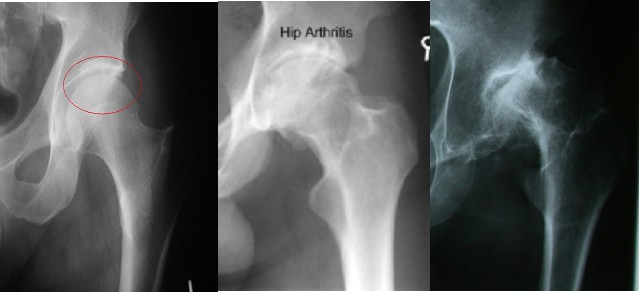

A simple x-ray should show changes of osteoarthritis. The x-ray findings classically include as joint space narrowing, subarticular sclerosis, osteophytes and degenerative cyst formation.